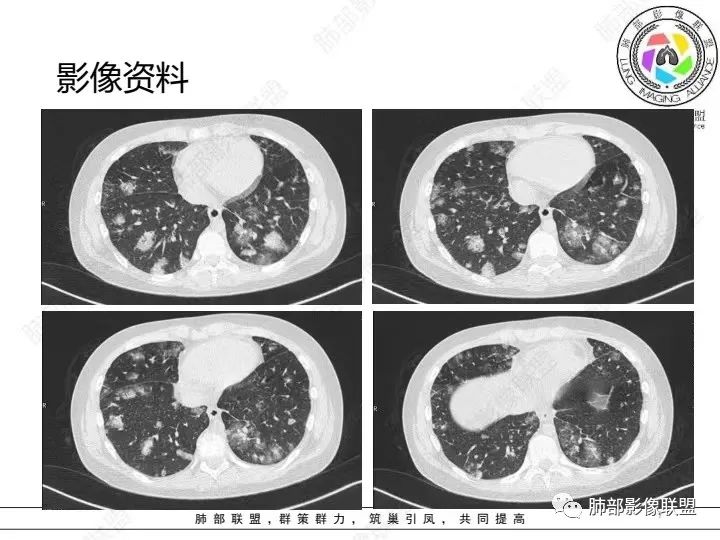

【病例】血源性金黄色葡萄球菌性肺炎1例CT影像

1.男性少年儿童,外伤后髋部疼痛,畏寒发热、咳嗽、呼吸困难。

休克血压。CRP、PCT明显升高。血气为代谢性酸中毒、呼吸性碱中毒。

2.影像上肺多发混合密度片影,随机分布,胸膜下分布优势,病灶边界大多隐约可辨,偏柔和,动脉血管影穿行,未见钙化、液化空洞、或明确气囊影,未见树芽征。

3.双侧胸腔未见积液。双肺门及纵隔未见增大淋巴结。

4.肝左右叶密度减低,未见结节影、块影或液化区。

血源性金黄色葡萄球菌性肺炎具有一些临床和影像学特征:

1.起病急,临床症状重;

2.表现多样,多种影像表现可同时出现,如斑片状影、小点状影、结节影、肺气囊等可在CT片上同时见到;

3.病灶比较广泛,多个肺野出现同时受累;

4.容易在短期内出现散在的肺气囊或多发的脓肿病灶;

5.病灶易变,短期内复查CT可见病灶的形态、部位、大小发生变化。

金黄色葡萄球菌肺炎CT征象 来源放射沙龙

1.外围分布,胸膜下为主,两肺弥漫结节或胸膜下楔形影,边界清,周围伴有GGO

2.反晕征:往往紧贴胸膜,并且胸膜侧无环,周围GGO

3.空洞:分为两类。

第一类,偏心空洞,一侧壁厚,周围实变明显。

第二类,薄壁空洞(偏中后期):壁薄且均匀,内外壁光滑,张力高,内有气液平面、间隔影,各空洞相对独立互不相通

4.囊:张力高,壁薄,内外壁光滑,可有间隔

5.边缘收缩明显,结节密实,边缘收缩、凹陷,周围长索条影,提示吸收好转

6.胸腔积液、脓胸